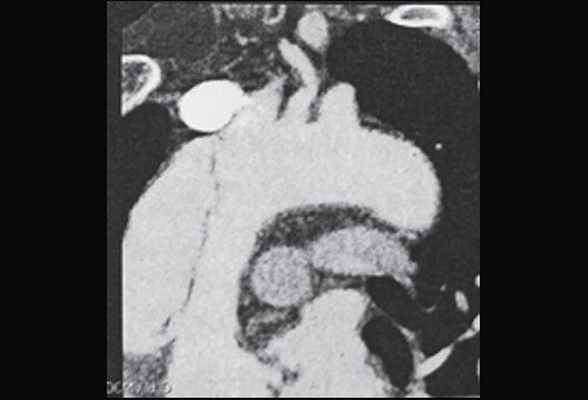

На основании серии поперечных срезов на рабочей станции выполнялись многоплоскостные и объемные реконструкции. По данным ЭЛТ, сразу за кольцом аортального клапана, диаметр которого составлял 3.0 см, начинается аневризматическое расширение восходящей аорты, достигающее 6.3 см в диаметре на границе между проксимальной и средней ее третями. Диаметр дуги аорты 3.5 см, нисходящей аорты - 3.3 см. Начиная от уровня синусов Вальсальвы, видна отслоившаяся интима, имеющая извитой ход и формирующая ложный канал вдоль задне-левой стенки аорты (рис. 6 а, b, с). Расслоение переходит на дугу аорты и заканчивается в ее дистальной трети. В нижней части отслоившейся интимы видна фенестрация размером около 2.5 см; в дистальном отделе дуги имеется второй разрыв интимы диаметром около 2.0 см. Тромботические массы в просвете ложного канала отсутствуют. При анализе состояния сосудов, отходящих от дуги аорты, обнаружен переход расслоения на устье брахиоцефального ствола.

Рис. 6. Электронно-лучевая томография.

а - срез в поперечной плоскости. В просвете аорты, заполненном контрастным препаратом, видна отслоившаяся интима,

b - реконструкция в сагиттальной плоскости. Визуализируется проксимальный разрыв отслоившейся интимы,

с - трехмерная реконструкция.